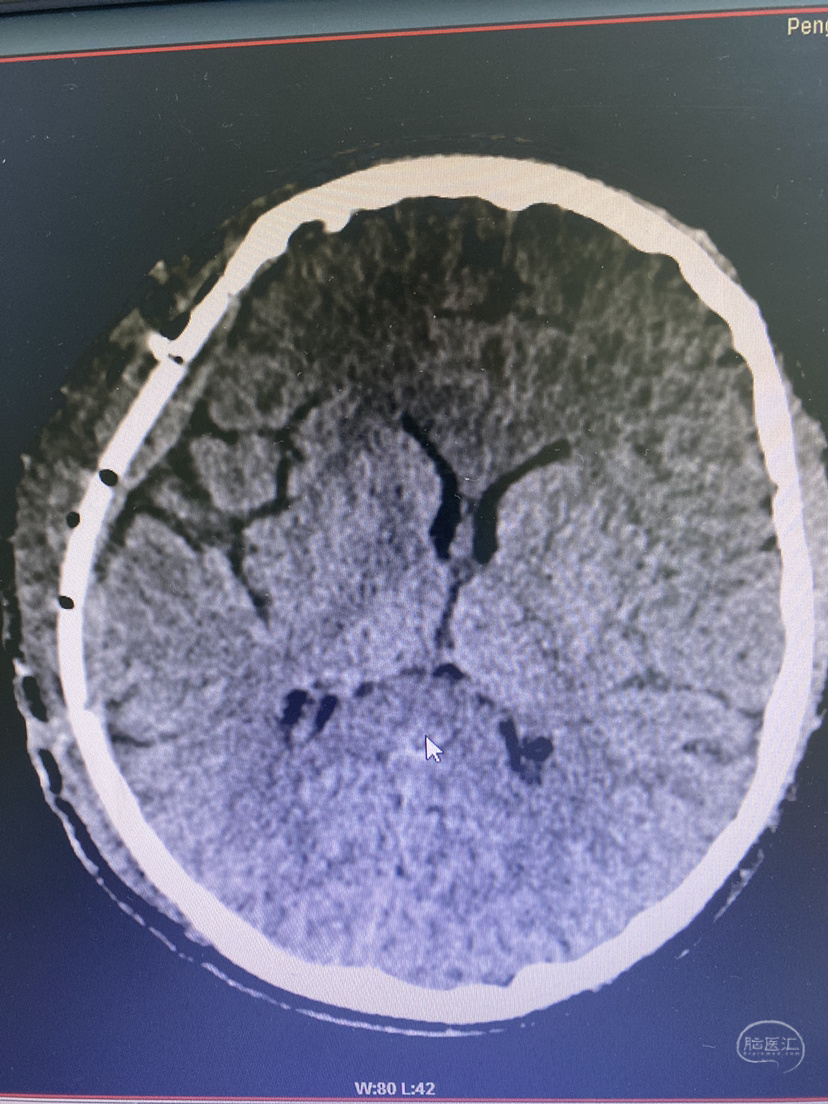

术后2月,修补前头颅CT